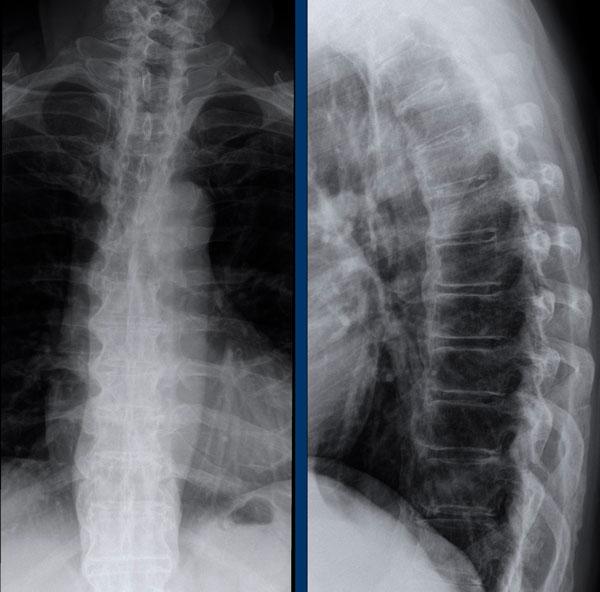

Cột sống tre

Hình ảnh cột sống tre trong viêm cột sống dính khớp.

Hợp nhất cột sống thắt lưng do gai xương syndesmophyte và vôi hóa dây chằng cạnh sống.

Lưu ý vôi hóa dây chằng (mũi tên).

Cột sống tre cứng đờ dễ bị gãy do cơ chế ưỡn quá mức, ngay cả sau chấn thương nhẹ.

Luôn cần nghi ngờ cao về các gãy xương này ở bệnh nhân có cột sống cứng!

Cột sống tre thường bắt đầu ở đoạn thắt lưng và có thể lan lên đến cột sống cổ.

Lưu ý hình vuông hóa thân đốt sống (mũi tên).